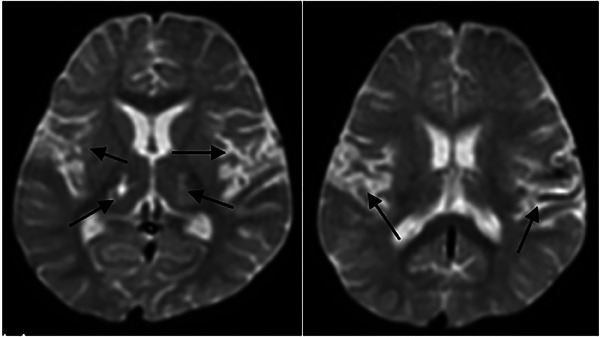

Results: All children exhibited different degrees of oral movement, dysphagia, and speech and language disorders. There was a significant difference between expressive and receptive language ability (P < 0.05). There were 10, 8, and 12 children who had an intellectual disability, limb disability, and epilepsy, respectively. In addition to the damage of the peri-tegmental cortex found in MRI, thalamus lesions occurred in 19 cases and white matter involvement in six cases.